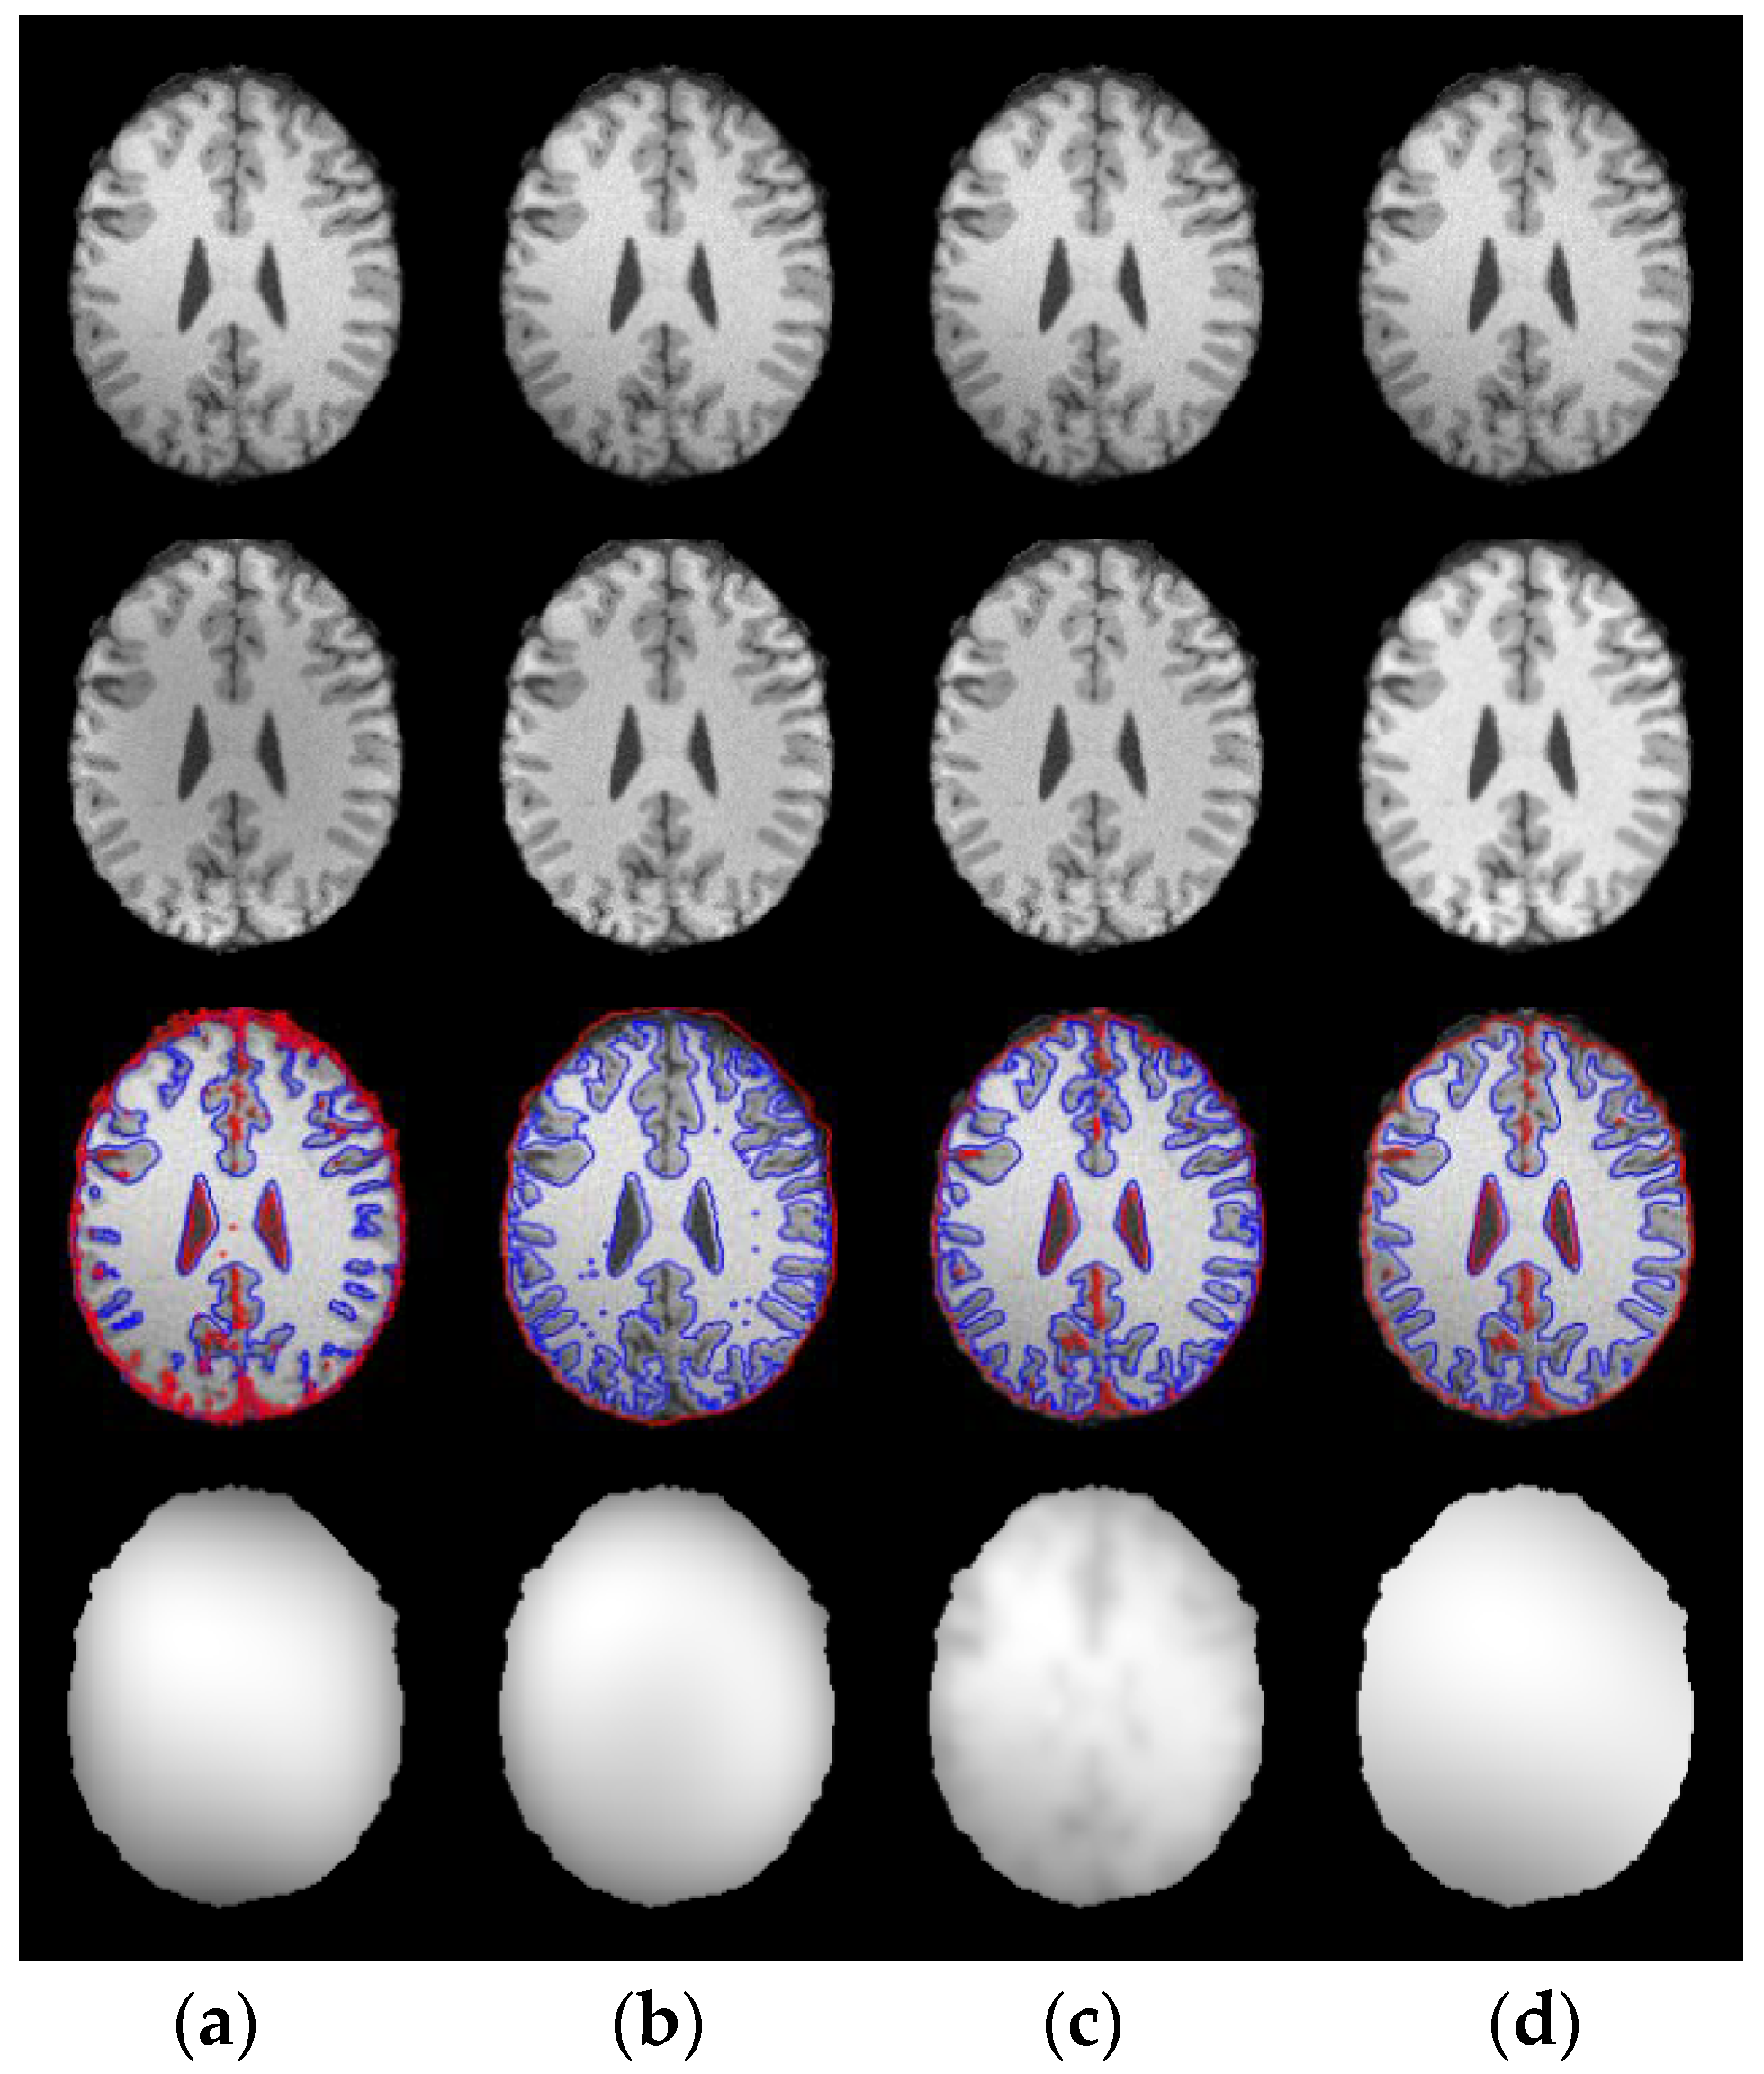

3.3. Results on Sagital, Coronal and Axial Slices of Images